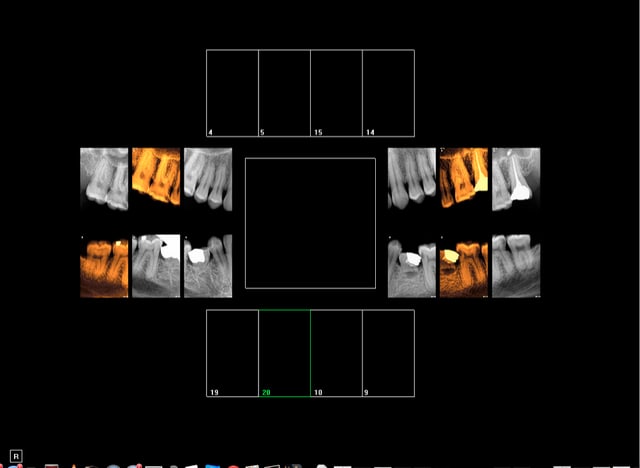

1h pour une consult ? J'en fait quasiment jamais de consult.

Ex : patient en urgence, douleur diffuse.

Bilan radio ext 75, 5 mn. Et il y a du boulot à suivre !

Je vais y passer beaucoup plus de temps et il va me dire c'est tout ? -))))